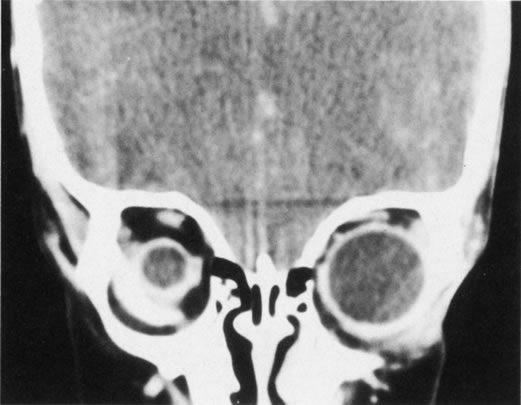

True cyclopia is a rare congenital anomaly characterized by a single eye situated in a single median orbit. Synophthalmos, which is also rare but much more common than true cyclopia, occurs when paired ocular structures are found in a single median orbit (Fig. 19). These disorders result from a failure of lateralization of the midline facial structures.

Fig. 19. Synophthalmos.